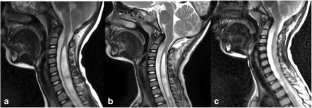

Chiari I malformation has been shown to present different cerebrospinal fluid (CSF) flow patterns at the cranial-vertebral junction (CVJ). Posterior fossa decompression is the first-line treatment for symptomatic Chiari I malformation. However, there is still controversy on the indication and selection of decompression procedures. This research aims to investigate the clinical indications, outcomes, and complications of the decompression procedures as alternative treatments for Chiari I malformation, based on the different CSF flow patterns at the cranial-vertebral junction. In this study, 126 Chiari I malformation patients treated with the two decompression procedures were analyzed. According to the preoperative findings obtained by using cine phase-contrast MRI (cine PC-MRI), the abnormal CSF flow dynamics at the CVJ in Chiari I malformation was classified into three patterns. After a preoperative evaluation and an intraoperative ultrasound after craniectomy, the two procedures were alternatively selected to treat the Chiari I malformation. The indication and selection of the two surgical procedures, as well as their outcomes and complications, are reported in detail in this work. Forty-eight patients underwent subdural decompression (SDD), and 78 received subarachnoid manipulation (SAM). Ninety patients were diagnosed as having Chiari I malformation with a syrinx. Two weeks after the operation, the modified Japanese Orthopedic Association (mJOA) scores increased from the preoperative value of 10.67 ± 1.61 to 12.74 ± 2.01 (P < 0.01). The mean duration of follow-up was 24.8 months; the mJOA scores increased from the postoperative value of 12.74 ± 2.01 to 12.79 ± 1.91 at the end of follow-up (P = 0.48). More complications occurred in the patients who underwent SAM than in those who received SDD (SAM 11 of 78 (9.5%) vs SDD 2 of 48 (3.5%)). The abnormal CSF flow dynamics at the CVJ in Chiari I malformation can be classified into three patterns. A SAM procedure is more feasible in Chiari I malformation (CM1) patients with pattern III CSF flow dynamics, whereas a SDD procedure is more suitable for CM1 patients with pattern I CSF flow dynamics. In CM1 patients with pattern II CSF flow dynamics, an intraoperative ultrasound after craniectomy could play an important role in the selection of an effective decompression procedure.